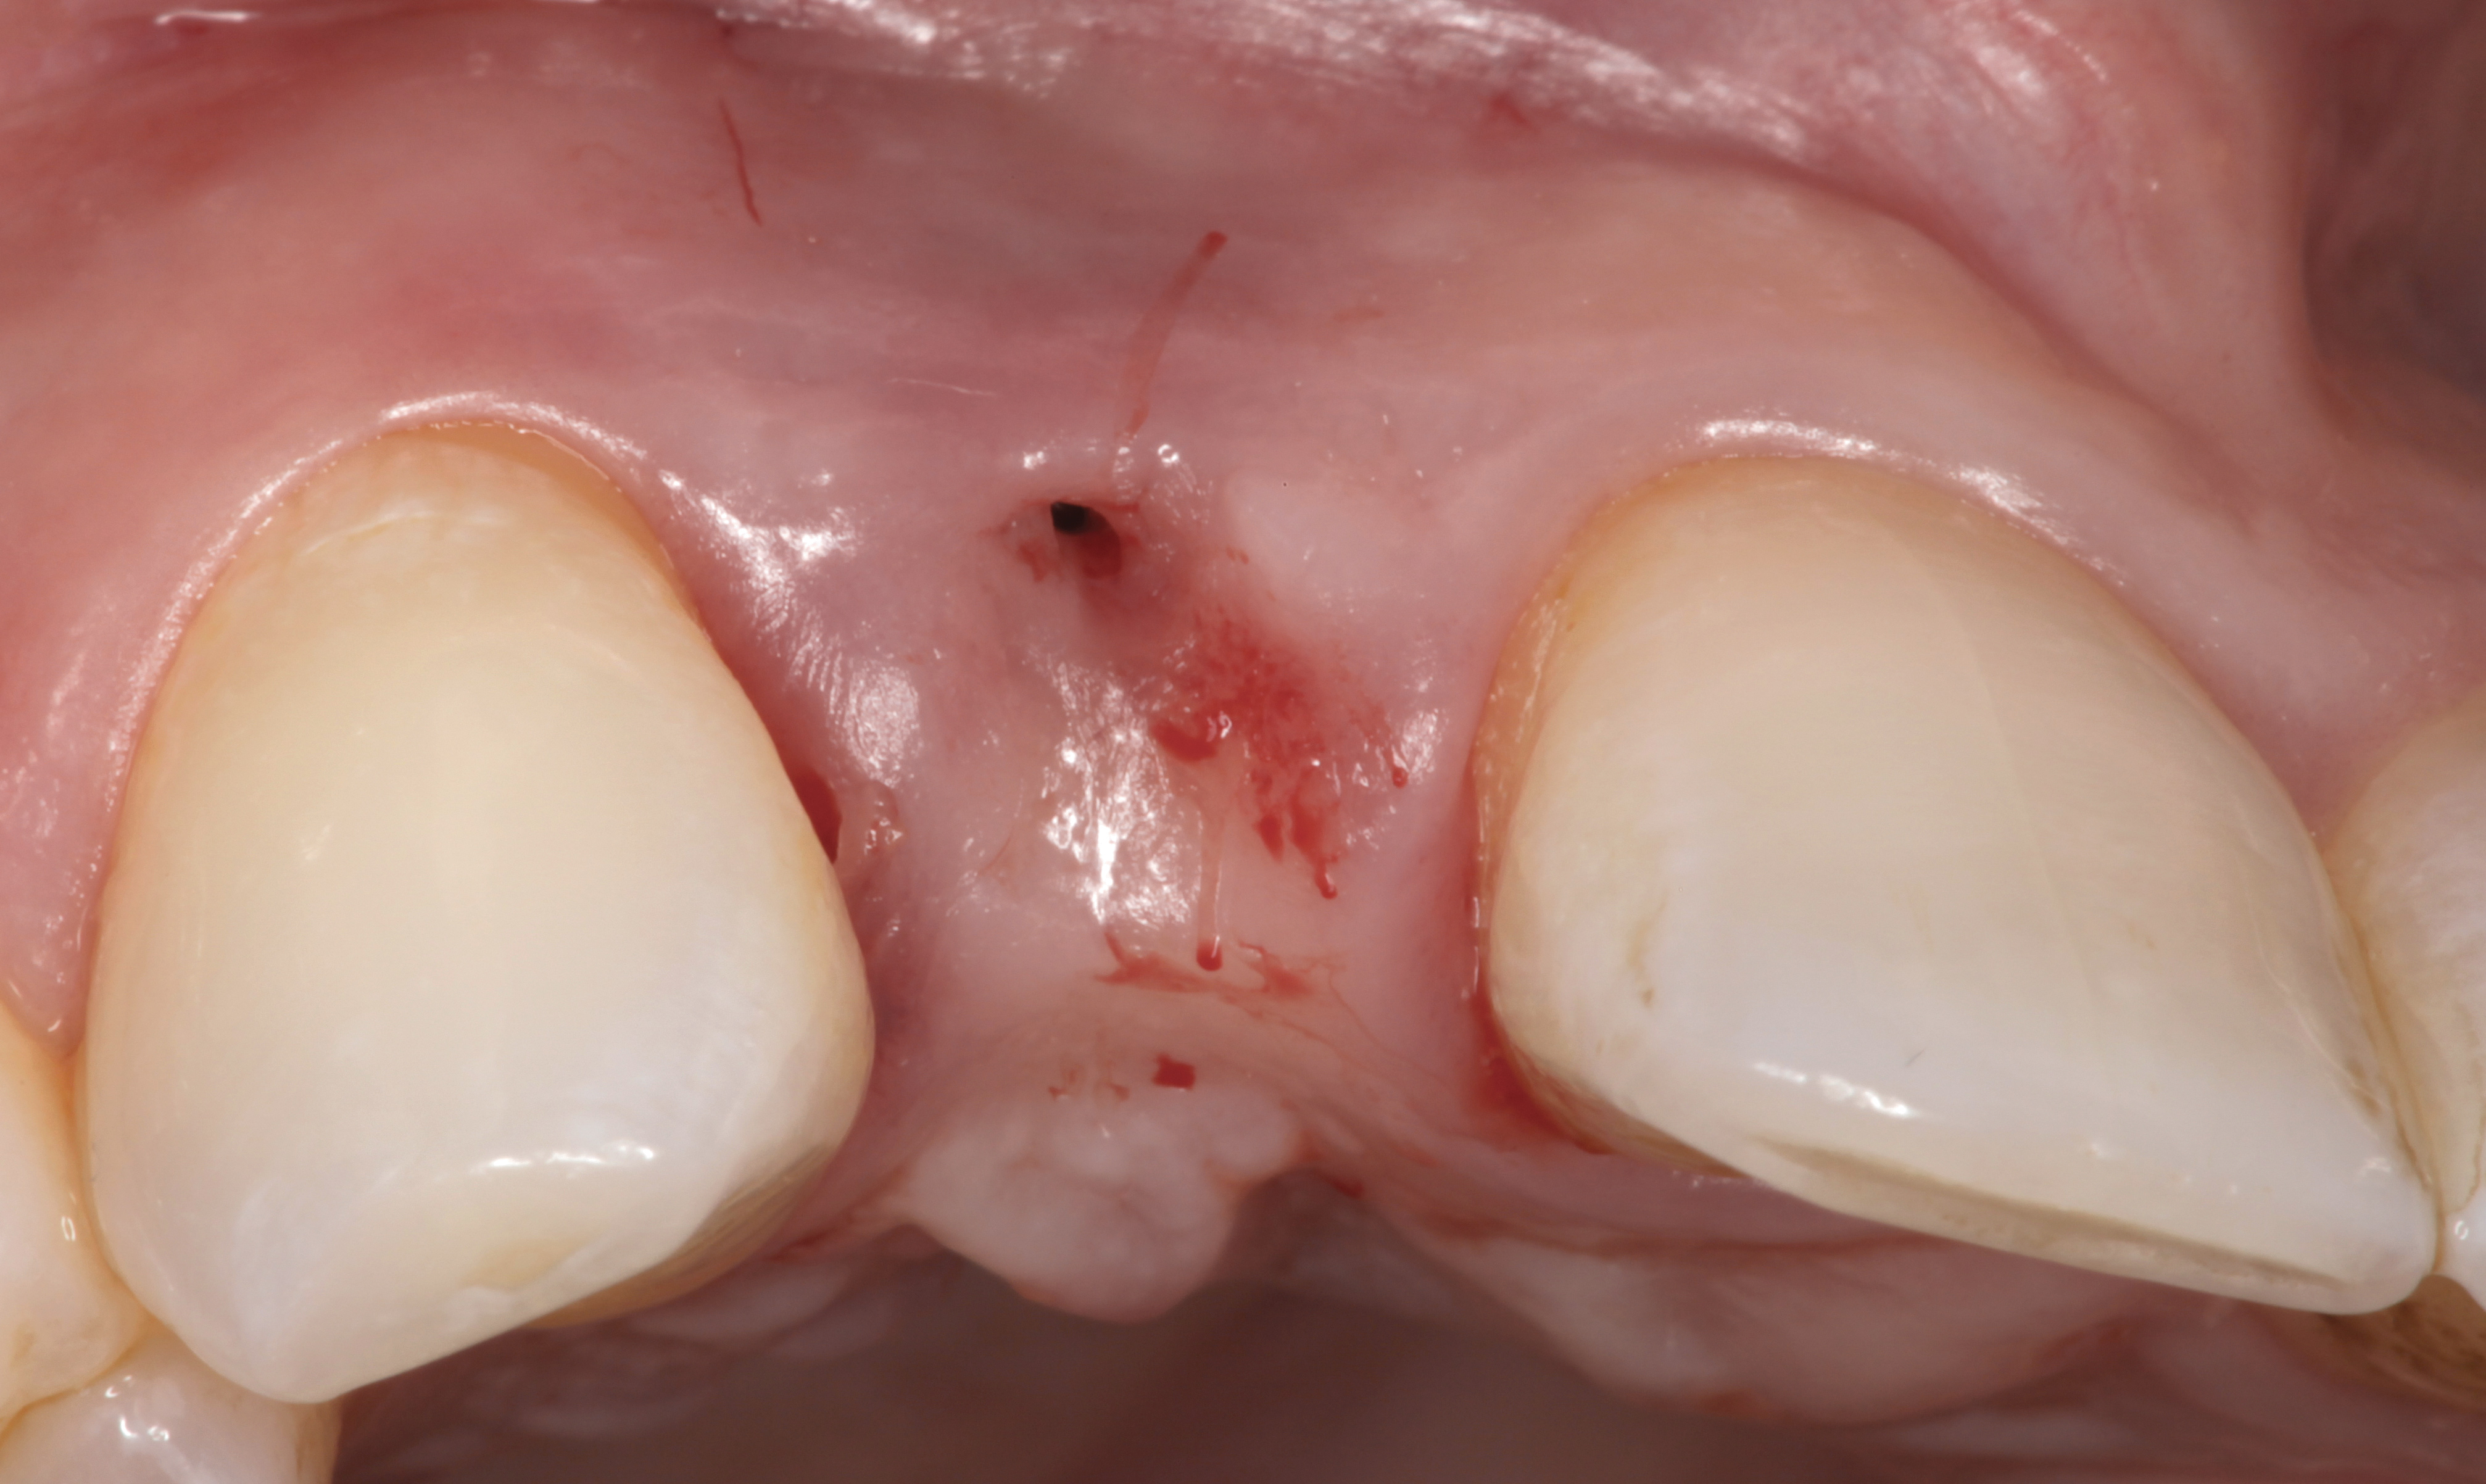

The following case report provides an example of this case scenario: A 24-year-old white male presented with congenitally missing tooth No. 26 restored with a single-tooth cement-retained implant restoration. The implant was placed excessively to the facial aspect of the edentulous site and too shallow, and the periodontal phenotype was thin scalloped (Figure 32). In an effort to mimic the lost midfacial soft tissues, pink ceramics were used as a cosmetic facade. Even though the restoration was not in the esthetic zone, the patient was highly displeased with the esthetic outcome and sought remediation.

The crown and screw-retained custom abutment were removed, and a surgical cover screw was placed into the implant, thereby allowing spontaneous gingival augmentation in situ (Figure 33 and Figure 34). Note that the lingual aspect of the implant site was significantly more coronal than the labial aspect, which was positive because the defect would be limited to a facial–lingual defect. A fixed RBR bridge was cemented on the adjacent teeth and used as a tooth-supported transitional provisional restoration (Figure 35). A few weeks were allotted to let the soft tissue heal and migrate around the cover screw (Figure 36) to see if there would be complete coverage, thereby allowing a soft-tissue augmentation procedure to be performed with primary flap closure as in clinical scenario No. 2. The major obstacle in achieving a positive tissue response was that the implant depth was also deficient because the implant–abutment connection was at the level of the free gingival margin. It was decided that the best treatment option would be to remove the implant. A high-powered reverse-torque device (Fixture Remover Kit, NeoBiotech, www.neobiotechus.com) was used to remove the implant atraumatically (Figure 38 through Figure 41). The implant socket was allowed to heal for several months not unlike an extracted tooth (Figure 42). A new implant was placed in a better position from both a restorative and esthetic perspective (Figure 43), and after a few months of healing, a new crown was made (Figure 44). A satisfactory functional and esthetic result was achieved (Figure 45 and Figure 46) without employing pink porcelain.

Fig 34. A surgical cover screw was placed in an attempt to decoronate the implant and gain soft-tissue coverage in situ.

Figure 34

Fig 36. Two weeks after RBR placement, the soft tissue did not adequately cover the implant. The problem was in poor implant angulation and proper depth to allow the soft tissues to cover over.